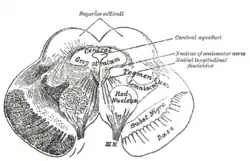

Transverse section through mid-brain. Transverse section of mid-brain at level of superior colliculi.

Transverse section of mid-brain at level of superior colliculi. Coronal section of brain immediately in front of pons.